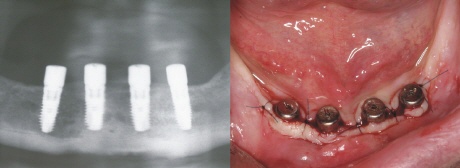

Einbringen der Implantate

In aller Regel können die Implantate in örtlicher Betäubung völlig schmezfrei in den Kieferknochen eingebracht werden. Der Wundbereich wird mit feinen Nähten verschlossen (Bild oben rechts). Der routinierte Behandler wird dazu nicht länger als zwischen 20 und 40 Minuten benötigen. Die Implantate heilen in diesem Fall unter der Schleimhaut (geschlossen) ein und die Fäden werden nach ca. sieben Tagen entfernt. Ein Röntgenbild direkt nach dem Einbringen der Implantate bestätigt die korrekte Positionierung.